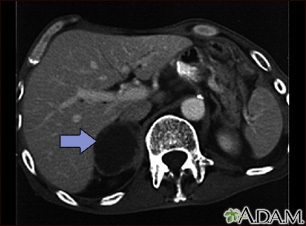

Adrenal metastases - CT scan

Adrenal metastases - CT scan

This CT scan of the upper abdomen shows an adrenal metastasis (spreading of a tumor to the adrenal gland, above the kidney) in a person with lung cancer.